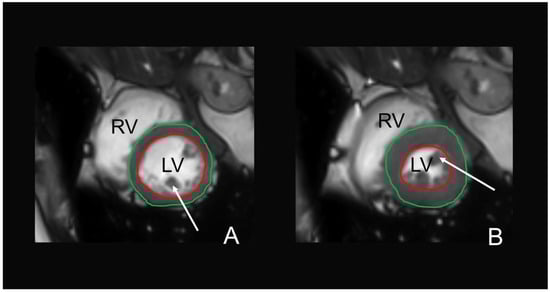

2.5. MR Image Analysis

2.8. MRI-Based Cardiac Function